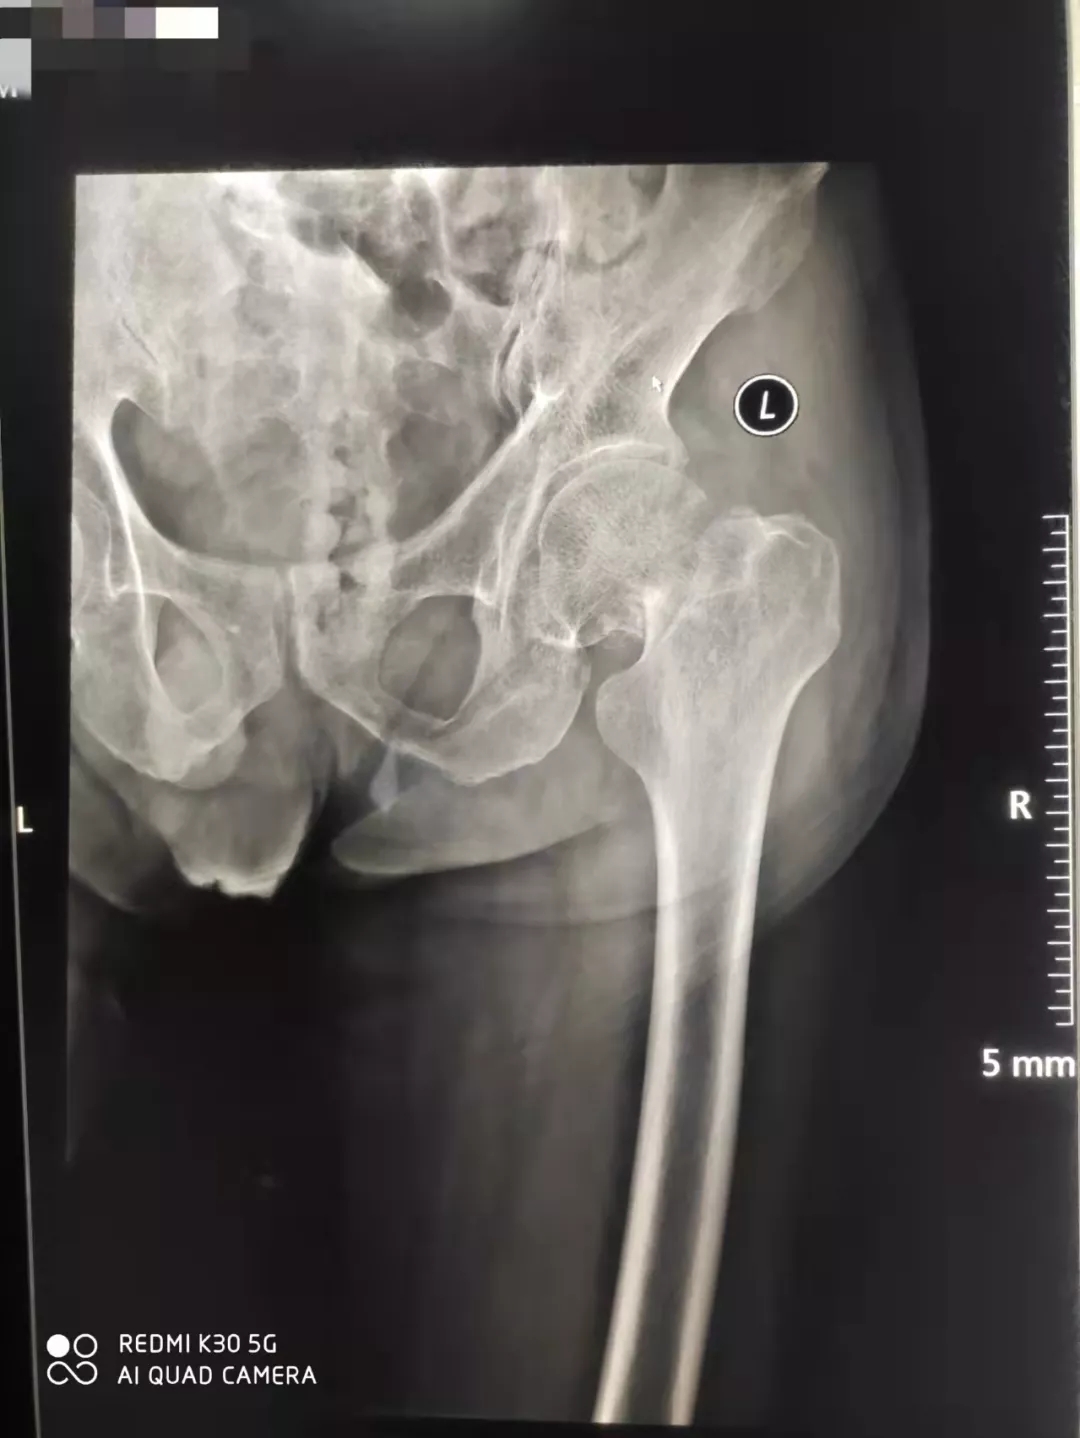

93岁的张爷爷不慎在家摔伤,左髋关节疼痛难忍,不敢活动,被家人紧急送至我院骨二科门诊就诊,检查提示左股骨颈骨折,入住骨二科治疗。

骨二科主管医生杨少洲接诊患者后,给予卧床制动,镇痛、补液、预防血栓等初步治疗。完善检查,评估患者的身体状况,经检查提示患者存在脑梗塞、脑积水、冠心病、缺血性心肌病、左前半束支传导阻滞、肾功能衰竭(代偿期)、贫血、电解质紊乱、高尿酸血症、骨质疏松等疾病。考虑患者年龄高、基础疾病多、手术风险大,告知患者家属病情及治疗方案和风险,经科室讨论后决定施行手术治疗,以便于患者早下床,减少卧床后的各种致命的并发症发生。请有关科室会诊后,骨二科为患者制定了详细周密的手术方案。凭借着丰富的临床经验和高水平创伤救治能力,在麻醉科的保驾护航下,骨二科团队用娴熟的手术技术,默契的团队配合,半小时内顺利完成左侧人工股骨头置换手术。术后24小时患者下床锻炼,1周后办理出院。